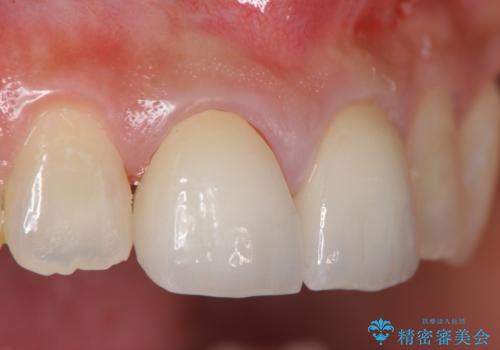

前歯をきれいにしたい

- 「 以前神経を取った歯の変色が気になる。前歯をきれいにして欲しい。」と治療を希望され来院されました。

目立つ上顎前歯に変色・大きな虫歯治療痕が見られ、審美障害を引き起こしています。

虫歯の徹底的な除去、根管治療を行いセラミック治療に入る前の環境をしっかりと整えたのち審美的なジルコニアセラミックで治療を仕上げました。